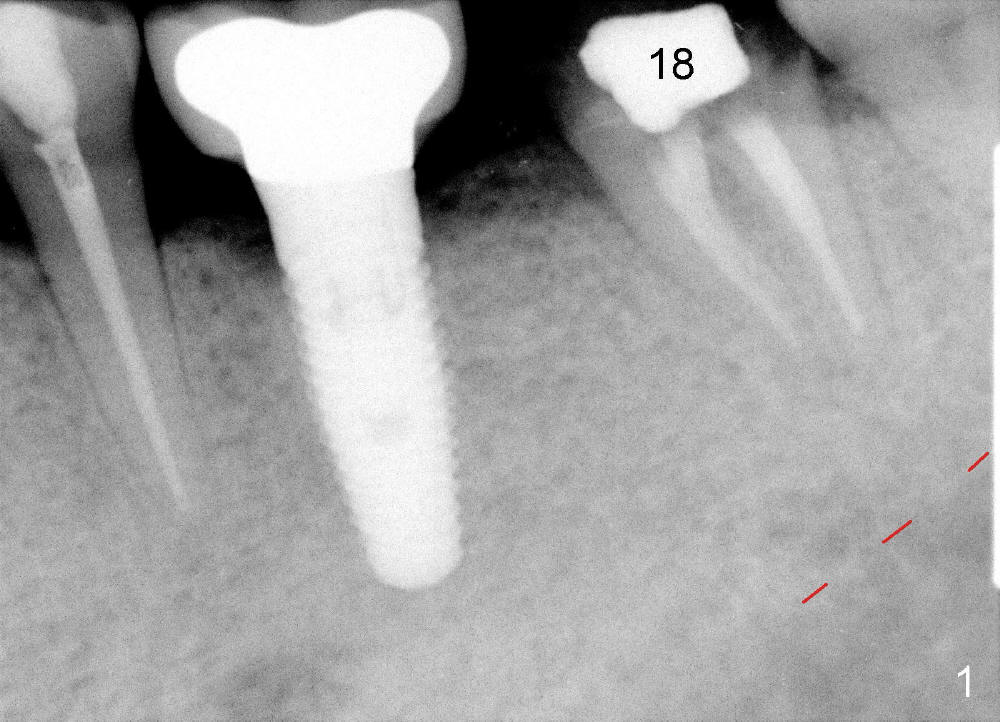

CBCT reveals periapical radiolucency (Fig.2 ^). The tooth appears to be nonsalvageable. The root is 11 mm long. There is 5 mm bone between the fused apex and the inferior alveolar nerve. The prospective implant is going to engage 3 mm out of the 5 mm native bone for primary stability.

The septum of the socket is thin (Fig.3*), and easily removed, leaving a large socket. Osteotomy is initiated with 2 mm pilot drill in the middle of the socket, slightly mesiolingual, since the buccal and distal bone is low and defective. Reamers (2.5 to 4 mm in diameter) are sequentially used to enlarge osteotomy and harvest autogenous bone (Fig.4 (3 mm reamer in place). When 5 mm tap is placed, there is no stability. Six mm tap gains some stability, but the socket is not closed. Seven mm tap achieves strong stability and is closing the socket (Fig.5). Ultimately a 7x14 mm implant is placed with insertion torque more than 60 Ncm (Fig.6). The implant almost obliterates the socket (Fig.7). The harvested autogenous bone is placed in the buccal and distal aspects of the socket before Chromic gut suture (4-0) is placed distally. Fig.8,9 show the healing socket 6 days and 1.5 months postop, respectively. Osteointegration appears to occur in 2.5 months (Fig.10, compare to Fig.6). Bone level remains the same 1 year post cementation (Fig.11).